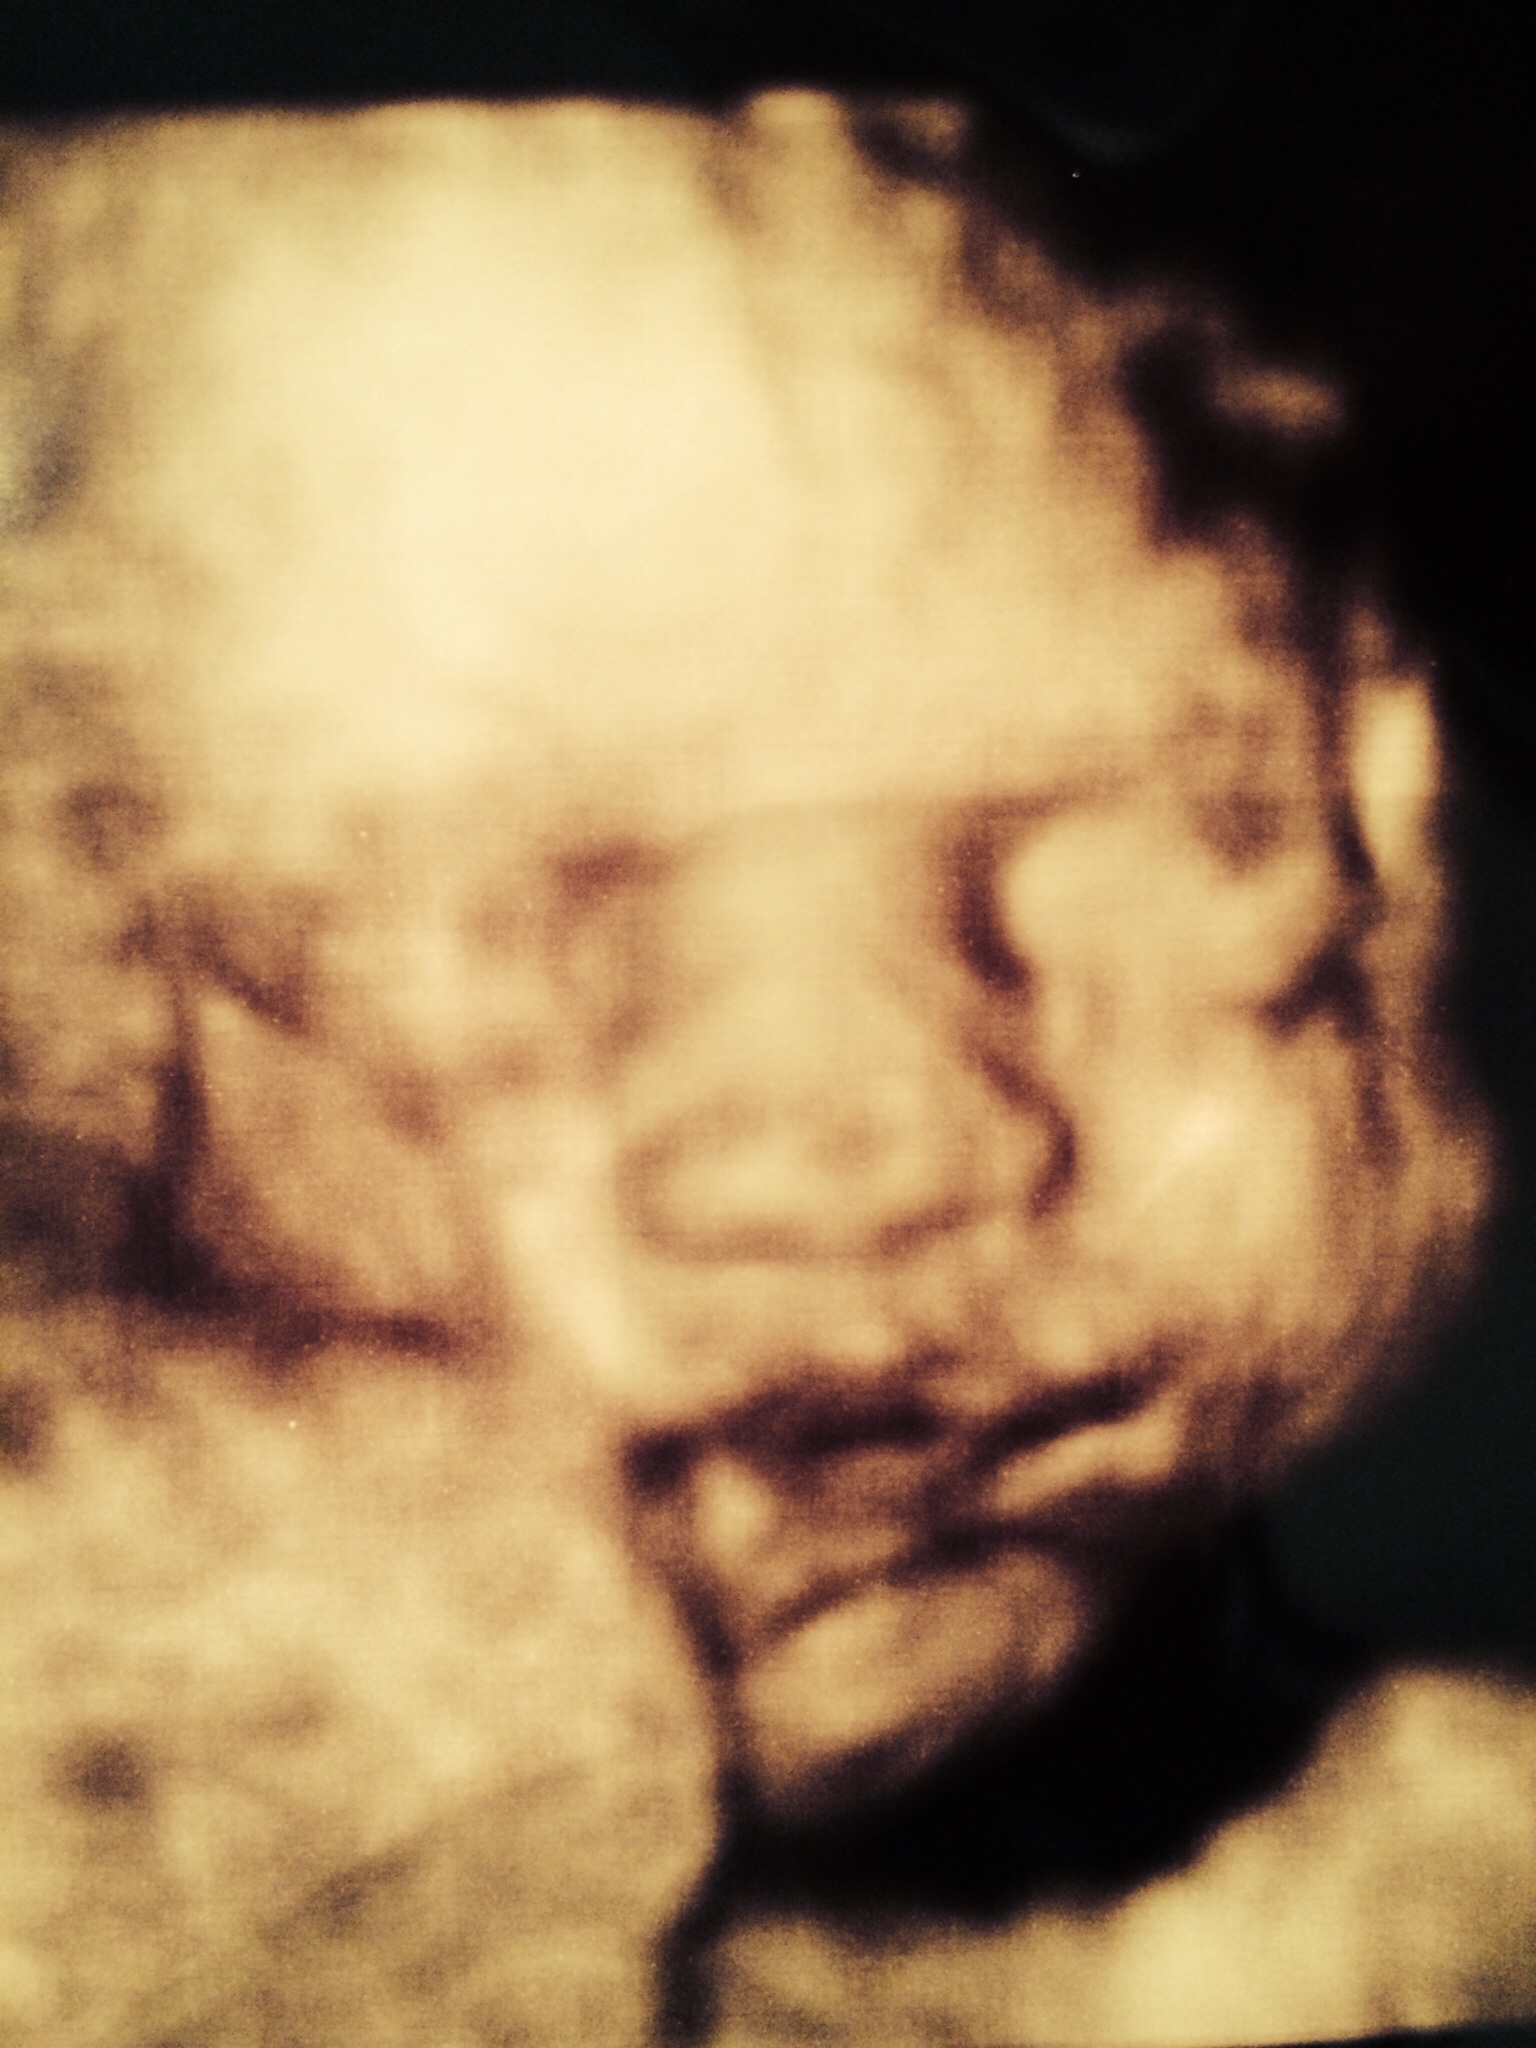

• She weighed 2 kilograms so I think it's 4 oz?(only know kg),length around 40cm. I only wanted to know if anyone had the same issue and how it turned out. You would think my midwife would be on top of it but with my 1st they weren't and now they don't seem to be. Every time i got for my app i have a different midwife. I went hospital about 1-2 weeks ago and they told me I measure fine and my muscles are just tight and I'm carrying her in the back whatever that means. Now this Tuesday I had 4d growth scan because wanted to see how my baba looks and the lady said that she's small but still within 28 weeks,today my midwife said she's behind and measures 25w so referred me for a scan. So I'm really confused